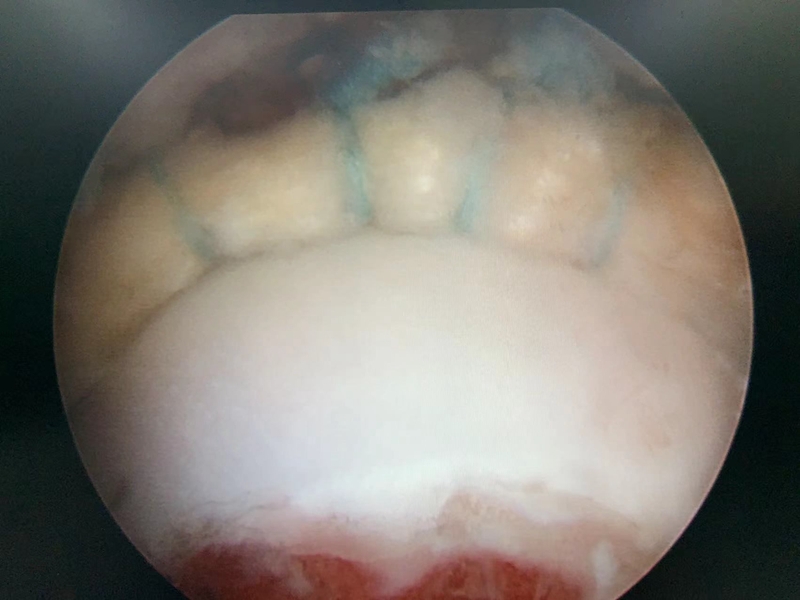

3.软骨损伤的处理:髋关节撞击综合征患者除了常常导致髋关节盂唇的损伤之外,还常常造成髋关节软骨的损伤,而且髋关节软骨损伤的部位也常常发生在髋臼的前方。目前对于任一关节的软骨损伤治疗都是难点,对于髋关节这样的负重关节更是如此。对于怀疑存在软骨损伤患者,则应早期进行手术治疗,尽可能避免髋关节退变的结局。

图11 撞击导致软骨损伤

病例,王X,女,32岁,反复活动后髋关节疼痛6月余,休息能缓解,诊断为髋关节撞击综合征合并盂唇损伤,规律保守治疗后无效,行髋关节镜下手术。

图12 术中